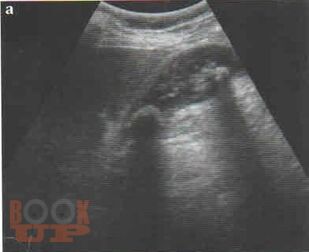

В учебном пособии представлена диагностика острого холецистита по данным ультразвукового исследования. Особое внимание уделено оценке положительных и отрицательных эхографических признаков острого холецистита на фоне проводимой терапии.